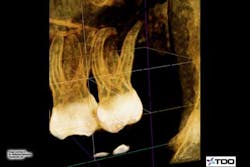

Description of the tooth, its position, and its root morphology: No. 15. Buccal inclination with four canals and the apical third curved slightly over 90 degrees to distal.

Diagnosis: Irreversible pulpitis with long roots and greater than 90-degree curvature.